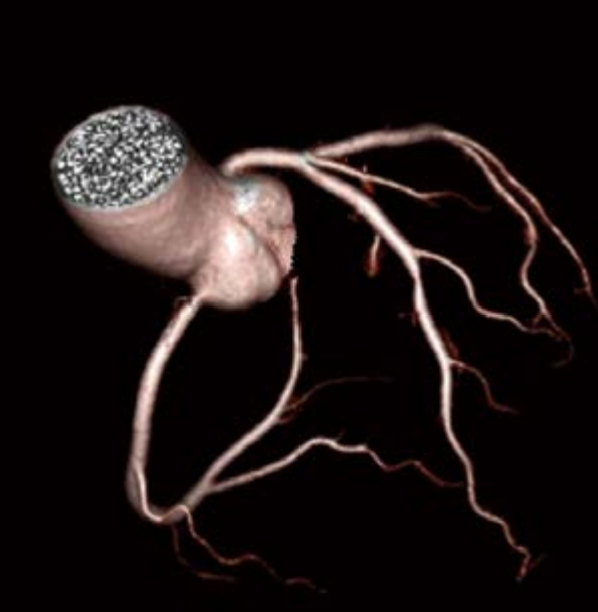

SinoVision Insitum 64s - это 64 срезовый КТ с большой апертурой гентри 75см. Один из самых доступных кардиологических компьютерных томографов. SinoVision Insitum 64 - это 64 срезовый КТ с большой апертурой гентри 76см. Уникальная интеллектуальная система управления стробированием SinoVision и алгоритм реваскуляризации коронарных артерий гарантируют мгновенное замораживание сердца и отображение структуры сердечно-сосудистой системы, стента, кальцификации, бляшек и другой информации в высоком разрешении.

- Интеллектуальная платформа коронарной визуализации мгновенно замораживает сердце и отображает информацию высокого разрешения о сердечно-сосудистых структурах, стентах, кальцификации и бляшках с помощью уникальной интеллектуальной системы управления и алгоритмов коронарной реваскуляризации SinoVision.

- Управление стробированием на основе модуляции в реальном времени - Система управления модуляцией синхронизации - Редактирование ЭКГ - Автоматический захват фазы - Отображение данных дыхательной волны - Встроенная система управления синхронизацией - Интеллектуальная аналитическая платформа

- Расширенный коронарный анализ

- Определяет степень стеноза и состав бляшки коронарной артерии, помогает при послеоперационном осмотре при шунтировании и стентировании

- Полностью автоматическая сегментация

- Полностью автоматическое извлечение

- Автоматическое обозначение кровеносных сосудов

- Удаление и измерение коронарных артерий с помощью искусственного интеллекта